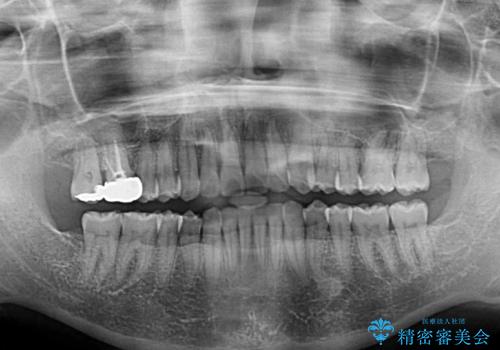

- 前歯のデコボコを治したいとのことで来院された患者様です。

上下顎ともに歯列全体の後方移動と側方拡大、IPR(歯と歯の間を削る)によってデコボコが解消するように設計し、インビザラインにより治療を行うこととしました。

後方移動に際し、上下の親知らずは4本とも抜歯することとしました。

治療途中で関西に転勤となってしまったため、東京に出張で来るタイミングに合わせて治療を進めることになりました。そのため、治療期間が長くなってしまいましたが、無事に仕上げることができました。